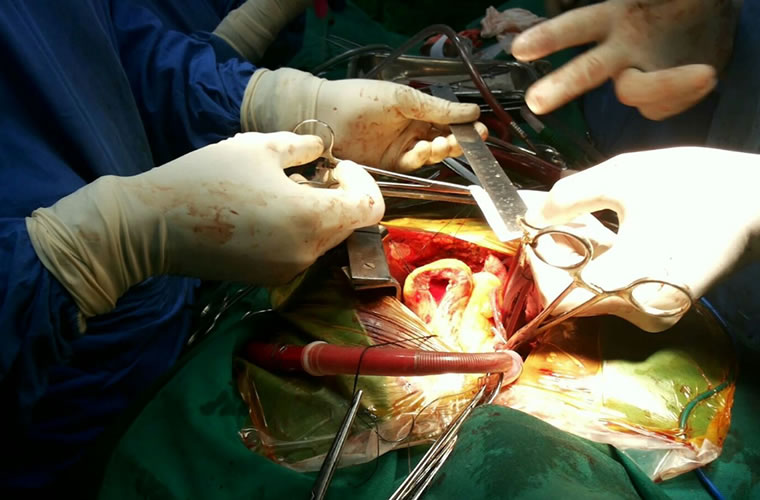

Dr.DineshShanmugaSundaram is specialized himself in each & every part of Cardiovascular & Thoracic Surgery both in Adult & Paediatric or Congenital Heart Diseases. He is both an ethical & academic surgeon,changed the trend in Cardiac Surgery to fast & safe level, as prolonged procedures in Cardiac Surgery increases postoperative complications. We aim at decreasing perioperative complications to the maximal level. Read More